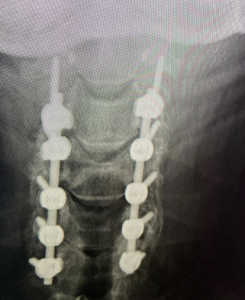

Here is a 64 y/o male who fell at home with resulting severe hand weakness and numbness due to cervical stenosis or narrowing of the spinal canal. The fall caused an injury to his spinal cord called myelopathy or a central cord syndrome. Central cord syndrome is a severe condition and can often result in permanent neurologic injury. Surgery (cervical laminectomy and fusion) was performed to relieve the pressure on the patient’s spinal cord and stabilize the spine. This patient responded very well to the surgery. In the days after surgery, he noted that his hands were stronger. By 6 weeks following surgery, he had recovered all of the normal function in his hands and arms.